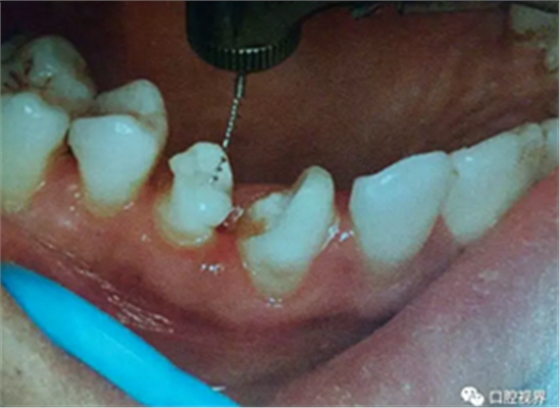

4.桩道预备时机和方法

预留桩道即刻桩道预备组的根尖和根中部粘结强度均明显高于延期常规桩道预备组,表明单纯从纤维桩粘结力考虑,预留桩道即刻桩道预备优于延期常规桩道预备,而延期常规桩道预备是目前常规操作方法,由此提示预留桩道即刻桩道预备具有可行性。